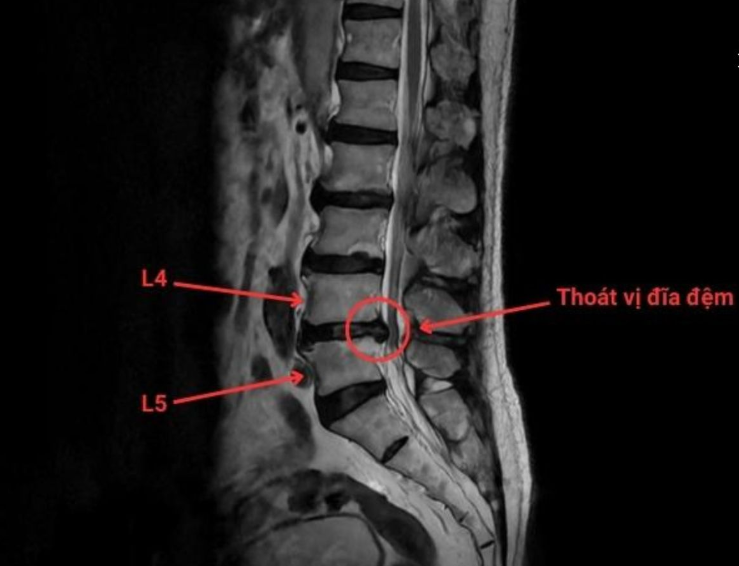

dau-dia-dem-1.png

Phim chụp thoát vị đĩa đệm cột sống thắt lưng L4/L5 - Ảnh BVCC

TS.BS Trịnh Tú Tâm, Trưởng khoa Chẩn đoán hình ảnh và Điện quang can thiệp, Bệnh viện Đa khoa Hồng Ngọc - Phúc Trường Minh cho biết: Thoát vị đĩa đệm là tình trạng nhân nhầy thoát ra khỏi vị trí ban đầu qua vết rách bao xơ, chèn ép vào rễ thần kinh và gây nên những cơn đau cấp và mạn tính. Trong điều trị, các phương pháp can thiệp điện quang ít xâm lấn đang trở thành xu hướng hiện đại, được áp dụng rộng rãi tại nhiều quốc gia trên thế giới.

Đau lưng do thoát vị đĩa đệm là một trong những bệnh lý cột sống thường gặp không chỉ ở người cao tuổi, mà còn có xu hướng trẻ hóa, trở thành “nỗi ám ảnh” với nhiều người bệnh.

Ban đầu, cơn đau thường chỉ âm ỉ vùng thắt lưng, nhưng theo thời gian cơn đau dần trở thành mạn tính, lan xuống hông và chân, kèm tê bì, rối loạn cảm giác và tiềm ẩn biến chứng như teo cơ, yếu chi, thậm chí liệt vận động, ảnh hưởng trực tiếp tới chất lượng cuộc sống và công việc.